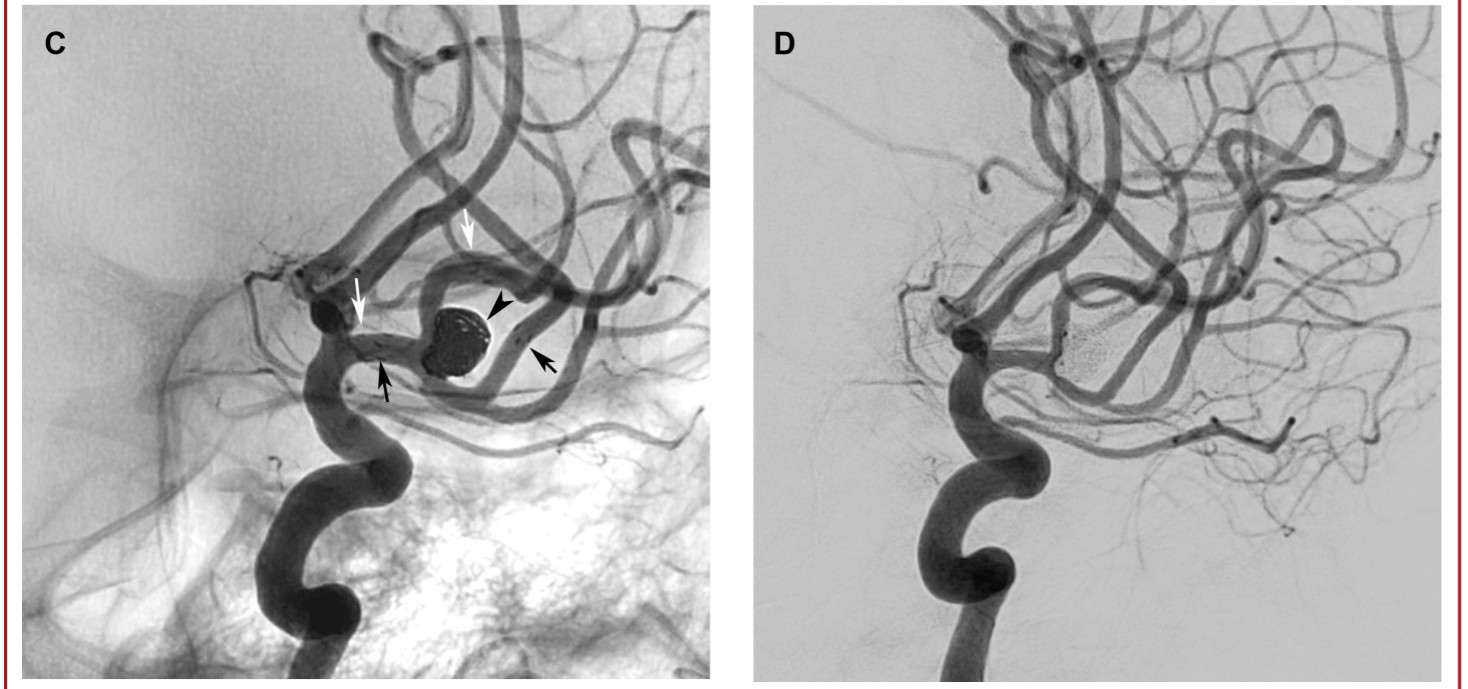

使用Neuroform Atlas支架用于Y型支架辅助栓塞技术,来治疗复杂性分叉动脉瘤。宽颈动脉瘤是指瘤体最大直径与瘤颈的比<2或颈径>4mm的动脉瘤。复杂的分叉动脉瘤定义为累及至少两个分支的宽颈分叉动脉瘤。在手术过程中,微导管超选时,首先在微导管到位困难的侧支血管内置入Excelsior SL-10(Stryker)微导管,然后另一个内径为0.0165英寸的微导管(Excelsior SL-10 or Headway 17; MicroVention/Terumo, Tustin, California)置入动脉瘤瘤体内。将第一个Neuroform Atlas支架释放到微导管到位存在困难的侧支血管内。随后以第一个Neuroform Atlas支架作为支撑,将同一Excelsior导管输送至第二分支,置入第二枚Atlas支架,与第一枚支架形成Y型支架。随后对动脉瘤进行致密栓塞。分别在术后即刻、术后3-6个月和9-15个月时进行DSA随访,采用Raymond–Roy (RR) 分级和载瘤动脉的畅通性来评估动脉瘤栓塞效果。采用改良的Rankin量表(mRS)对患者术前、术后即刻、出院、术后3-6个月和9-15个月的神经系统状况进行评估。记录患者术后出现的全部不良临床症状或体征,及围手术期和延迟并发症情况。

本研究回顾性分析了30例动脉瘤患者(20名女性)(表1)。纳入研究患者的平均年龄为52.4±8.9岁(34-66岁)。动脉瘤的瘤体最大直径为6.9±2.2 mm(4-16 mm)(图1)。分叉侧支的平均直径为2.2±0.3 mm(范围1.6-2.9 mm)。在支架展开或动脉瘤填塞的过程中,无操作相关并发症。术后即刻造影显示RR分级1级,2级,3级的患者例数分别为25例(83.3%),4例(13.3%),1例(3.3%)。无患者死亡,术后即刻神经系统检查较术前无变化。DSA造影随访平均时间为11.8±7.8月(6-36 月)。2名患者(6.7%)发生了围手术期(3.3%)或延迟并发症(3.3%)。上述延迟并发症导致患者永久性致残(3.3%)。全部患者的最终随访DSA结果显示:28例患者达到RR 1级闭塞(93.3%),2例患者实现RR 2级闭塞(6.7%)(表2)。在30例患者中,有28例患者临床随访显示mRS评分为0分。发生延迟性缺血性并发症的患者最终mRS评分为4分。一名术前mRS评分为2的患者术后随访mRS评分没有任何变化。